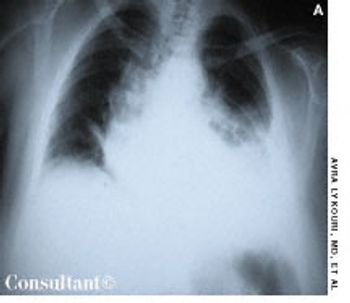

A 44-year-old black man presented to our office with insidious onset of blurred vision. He had no significant past medical history but complained of dyspnea on exertion. On examination, the left pupil was irregular and fixed. A chest film demonstrated bilateral hilar adenopathy. Laboratory findings included normal purified protein derivative test results and elevated angiotensin-converting enzyme levels; pulmonary function studies appeared normal.